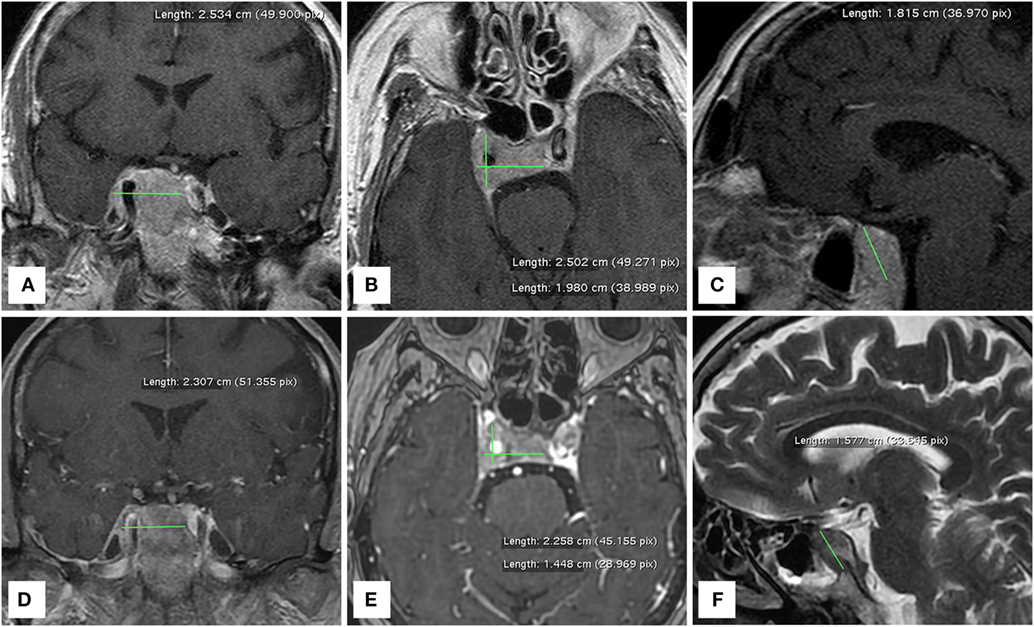

At our first observation in May 2017, basal Tg was 500 ng/ml, Tg-Ab <20 U/ml, TSH 0.015 mU/l, and daily levothyroxine intake was 137.5 mcg. Diplopia and right palpebral ptosis had started about 1-month earlier. A subsequent 18FDG PET/CT scan showed intense glucose metabolism in the basisphenoid region (Figure 1) and a gadolinium-enhanced brain MRI scan revealed a mass in the right cavernous sinus measuring 2.5 cm × 2.0 cm × 1.8 cm, with a low signal in T2 and enhancement on post-contrast images, which was compatible with a metastasis. The lesion encapsulated a 2-cm segment of the right internal carotid artery, without causing luminal narrowing (Figures 2A–C). Given the patient’s non response to RAI treatment and the locally advanced and progressively increasing metastatic burden, lenvatinib was initiated in June 2017. Because the intracranial lesion encapsulated a considerable portion of the right internal carotid artery, we started with a low dose (10 mg daily) to avoid the risk of artery damage consequent to rapid tumor shrinkage. An MRI performed about 30 days later showed that the metastasis in the right cavernous sinus was significantly smaller and that the integrity of the internal carotid was preserved (Figures 2D–F). Diplopia and palpebral ptosis progressively regressed with treatment and the patient did not complain of any cerebral symptom. Basal Tg declined to 338.4 ng/ml without Tg-Ab, in line with a reduction in neck lesions volume (Figure 3).

Figure 2. MRI brain scans performed before (A–C) and one month after (D–F) the administration of lenvatinib. The right cavernous sinus metastasis completely encapsulates a consistent portion of the intracranial tract of the right internal carotid artery.